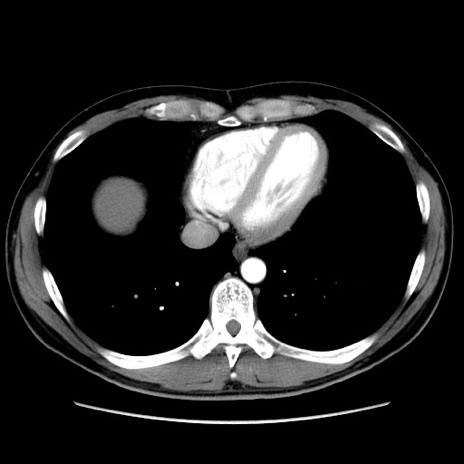

症例36(横断像)

【症例】20歳代 男性

【主訴】心窩部痛

【現病歴】今朝より上腹部痛あり。一旦軽快していたが再度出現したため救急要請。昨日夕に白身の魚を含む刺身を食べた。

【身体所見】BP 136/89mmHg、HR 74/min、BT 37.0℃、腹部:膨満、軟、心窩部に圧痛あり。反跳痛なし、筋性防御なし、腸雑音やや亢進あり。

【データ】WBC 17700、CRP 0.48